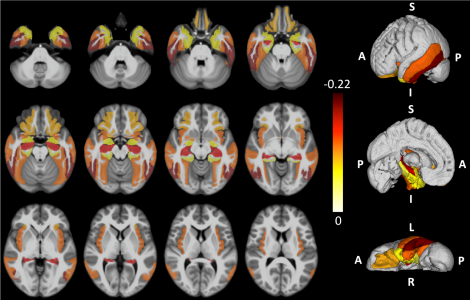

Dans leur article, les auteurs relient des observations de cliniciens, et les données neurobiologiques issues d'autopsies. Ils distinguent 3 stades de la maladie, caractérisés par l'étendue des régions atteintes par les lésions : d'abord l'amygdale seule (stade 1) rejointe par l'hippocampe (stade 2) et le gyrus frontal moyen (stade 3). D'un point de vue neurobiologique, LATE est liée à la présence de la version phosphorylée de la protéine TDP-43. Cette dernière intervient dans de nombreuses voies métaboliques, et reste normalement confinée dans le noyau. Depuis 2006, on sait qu'il existe une forme phosphorylée capable de pénétrer le cytoplasme, et est associée à l'apparition de lésions visibles à l'IRM. « Il reste à savoir si c'est un simple marqueur ou une cause de la maladie, ajoute le Pr Krolac Salmon, mais il existe des arguments génétiques en faveur de son rôle précoce dans la maladie ».